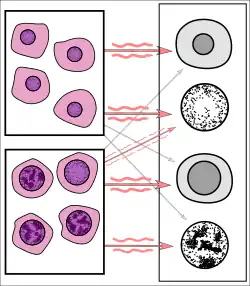

![Breast cancer prediction by AI.[17]](./_assets_/Histopathology_of_tumor_identification_by_AI.png) Breast cancer prediction by AI.[17]

Breast cancer prediction by AI.[17]